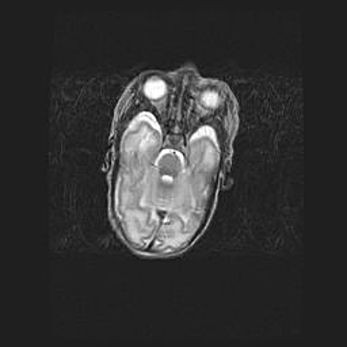

Наружная гидроцефалия с возможной атрофией височных областей.

Возраст: 28 дней

Вес: 3670 г

Пол: мужской

Окружность головы: 38 см

Срок гестации: 40 недель

Гидроцефалия головного мозга у новорожденных – это заболевание, которое характеризуется скоплением избыточного количества спинномозговой жидкости в желудочковой системе головного мозга в результате затруднения её перемещения от места выработки к месту поглощения в кровеносную систему или вследствие нарушения абсорбции. При открытой наружной форме гидроцефалии у новорожденных расширяются и переполняются субарахноидные пространства.

При нормотензивных  формах,  которые,  как  правило,  являются  следствием  перенесенных ишемических  повреждений  паренхимы  мозга,  возможно  сочетание микроцефалии  с нормотензивной гидроцефалией. В основе данных изменений лежит атрофия больших полушарий с преимущественной  локализацией  в  лобно-височных  областях.